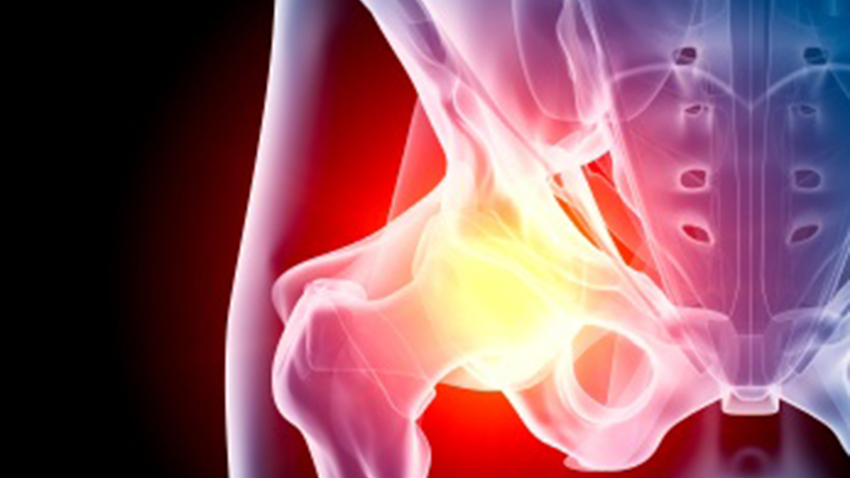

Physiotherapy - Hips

There are a variety of reasons why you might seek out a physiotherapist for hip problems. Bursitis of the hip is the most common cause of hip pain. Osteoarthritis, a degeneration of cartilage in the hip joint, is another. Rehabilitation after hip replacement surgery (often due to arthritis) usually requires the help of a physiotherapist. Athletes can suffer a hip flexor strain when the muscles are overused, overstretched, or forced to hyperextend. Many hip conditions are age-related, such as hip fracture or breakage.

There are a variety of reasons why you might seek out a physiotherapist for hip problems. Bursitis of the hip is the most common cause of hip pain. Osteoarthritis, a degeneration of cartilage in the hip joint, is another. Rehabilitation after hip replacement surgery (often due to arthritis) usually requires the help of a physiotherapist. Athletes can suffer a hip flexor strain when the muscles are overused, overstretched, or forced to hyperextend. Many hip conditions are age-related, such as hip fracture or breakage.

Physiotherapy for Hip Replacement/Injuries

Types of Physiotherapy for the Hip